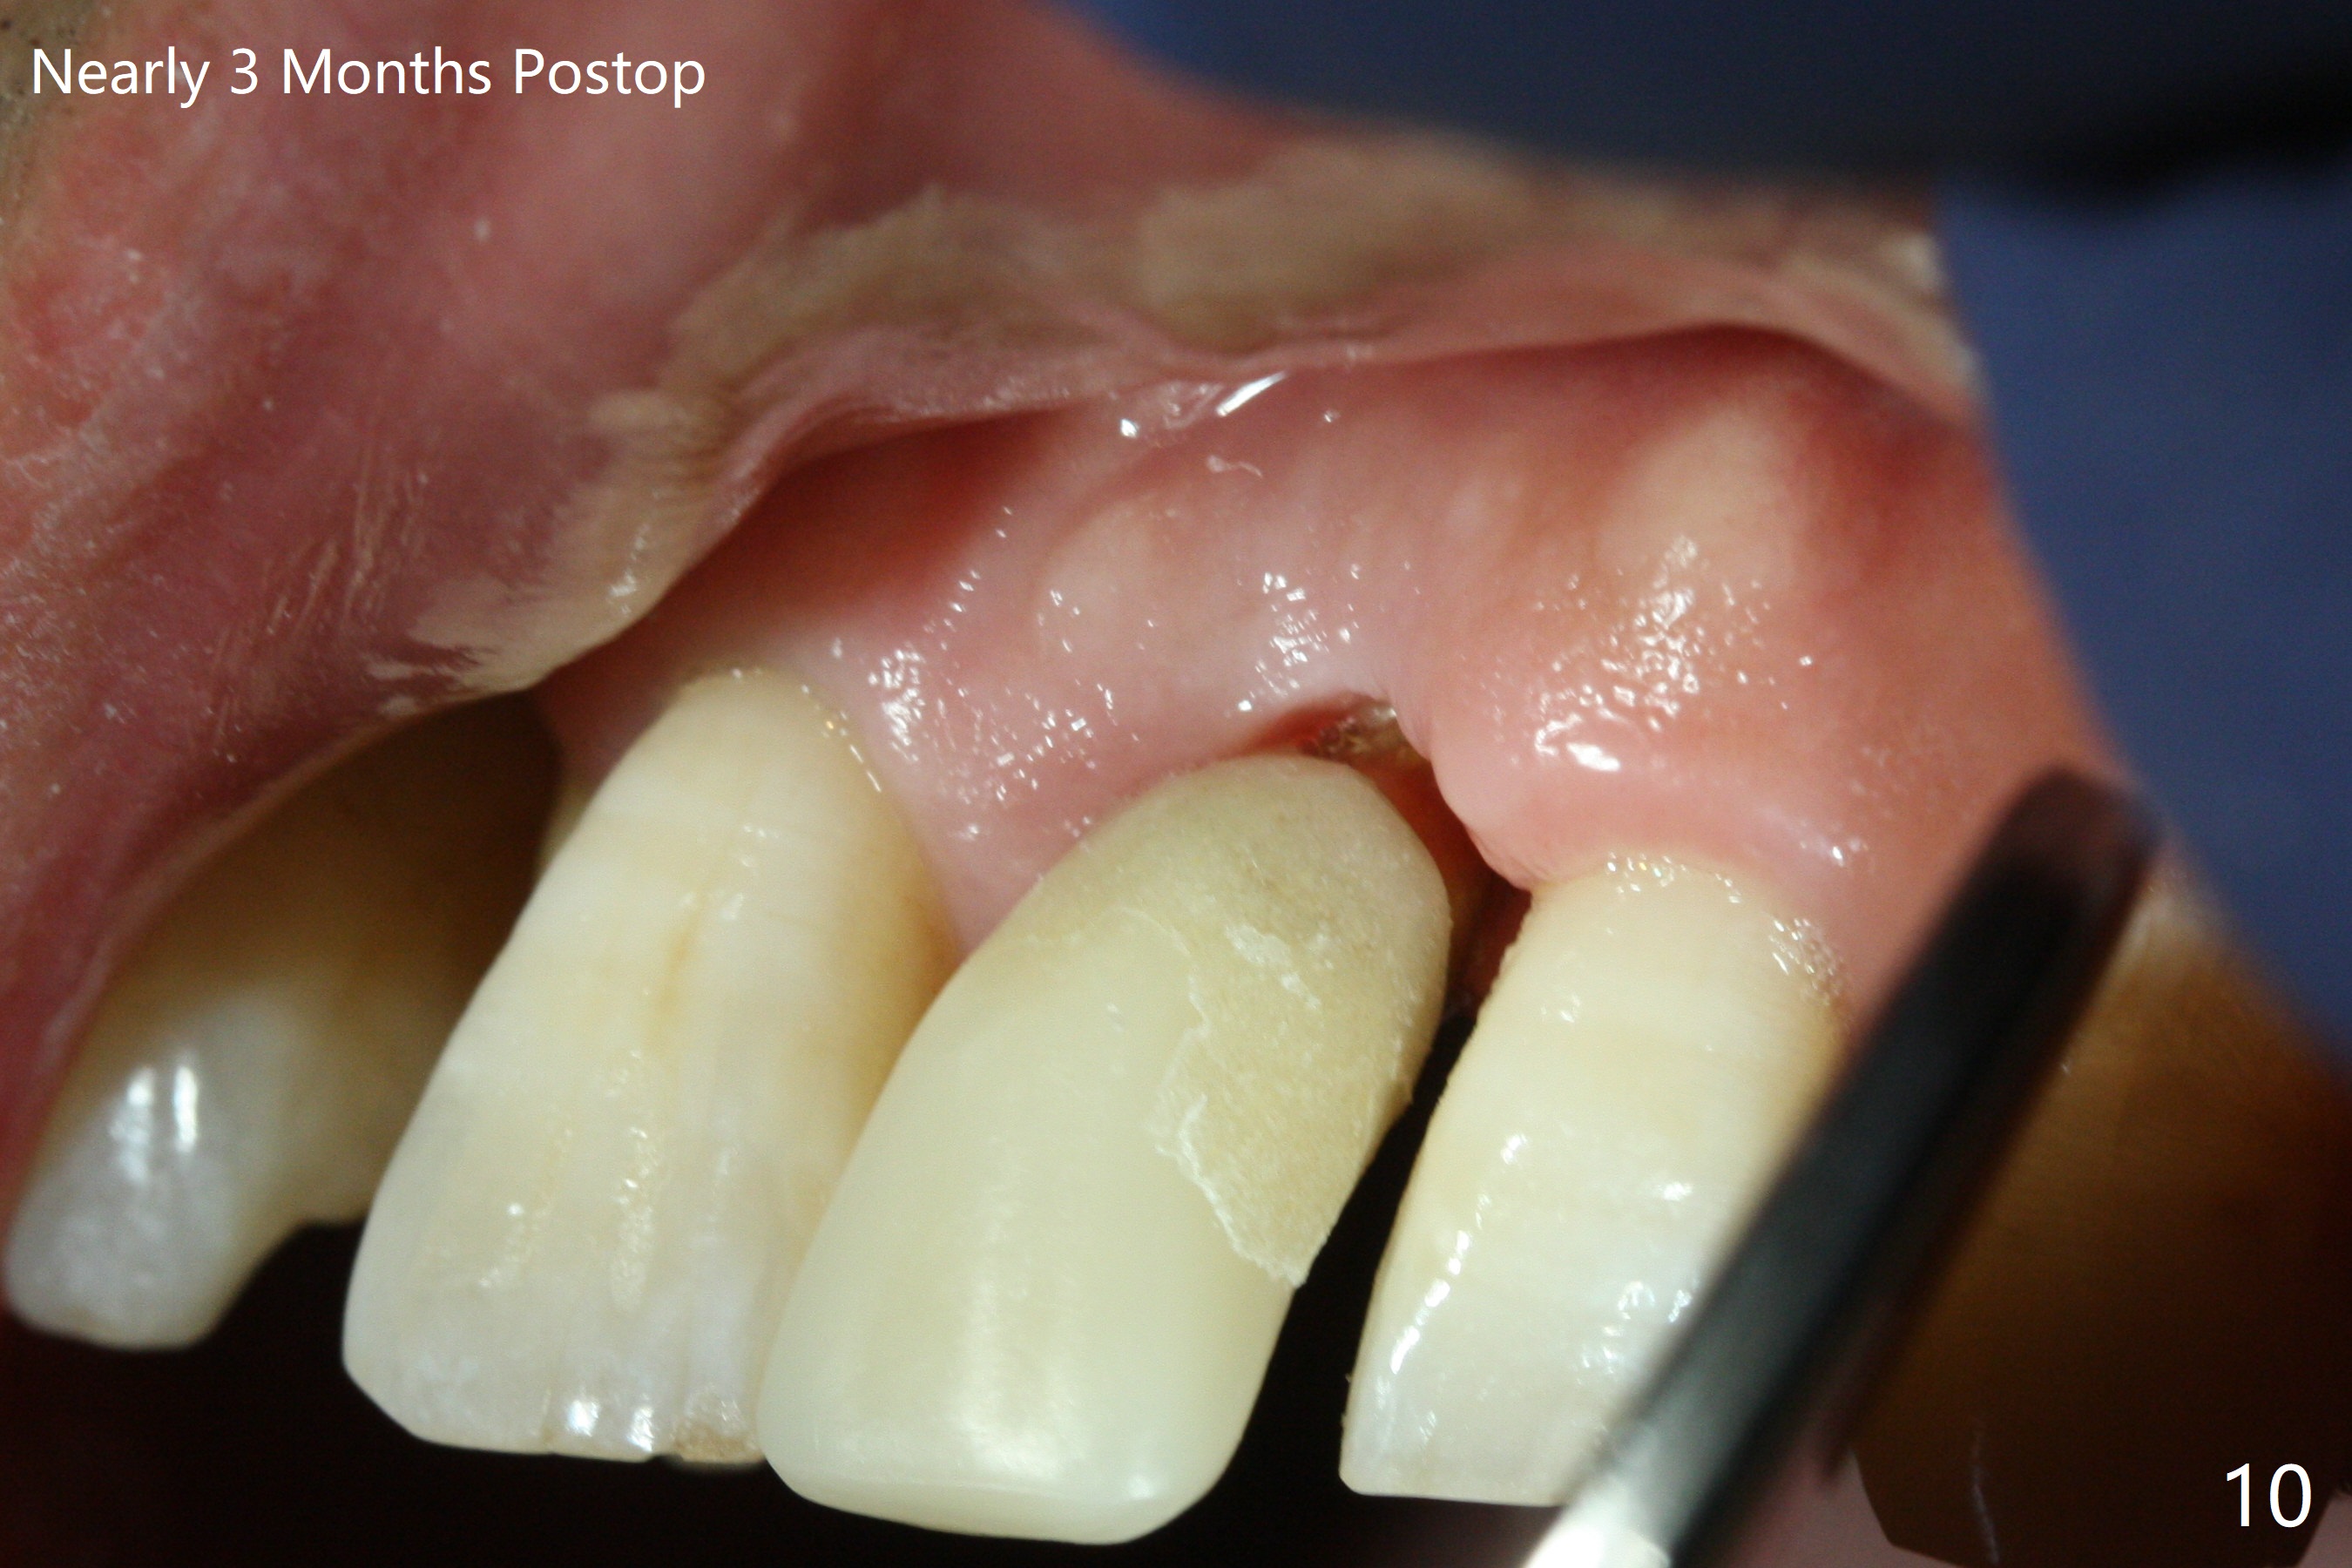

Immediately preop PA confirms loss of the buccal plate at #9 (Fig.1 *). In contrast the palatal crest is ~ 4 mm subgingival (WNL) after extraction. When initial osteotomy reaches 18 mm, there is moderate hemorrhage, probably due to close to the nasal floor (Fig.2 red dashed line). Following sequential osteotomy, a 3.8x15 mm dummy implant is placed partially (Fig.3 (pink: apical osteotomy)). After placement of an implant with the same dimension as the dummy's (Fig.4), PRF is laid against the inner surface of the buccal defect and allograft (Fig.5 *) is packed mainly in the buccal gap before and after insertion of a 4.5x5(4) mm abutment. The patient is satisfied with the immediate provisional (Fig.6: 1 week postop). The buccal margin of the provisional is shortened with exposure of bone graft to facilitate gingival downgrowth (Fig.6: 1 month postop). The buccal plate seems to collapse nearly 2 months postop (Fig.8 *), probably due to loss of the bone graft. The abutment is exposed buccally (Fig.9). The margin of the abutment is reprep and the provisional is relined so that the margin of the provisional is palatal to the buccal gingival margin. In 2-3 weeks, a temporary abutment will be used to bulk the buccal gingiva. The gingiva seems to have downgrown; the buccal plate collapse appears normal nearly 3 months postop (Fig.10). The patient is more concerned about cross bite at #7. A temporary abutment is not used. The bone graft remains in place 3.5 and 4.5 months postop (Fig.11,12 *). Between 3 and 4 months postop, the mesial surface of the abutment has been trimmed (Fig.12 >). Since the mesial surface of the tooth #10 will be reduced (white curved line) to correct the upper dental midline, an angled abutment (red line) seems to be necessary to shift the provisional distal.